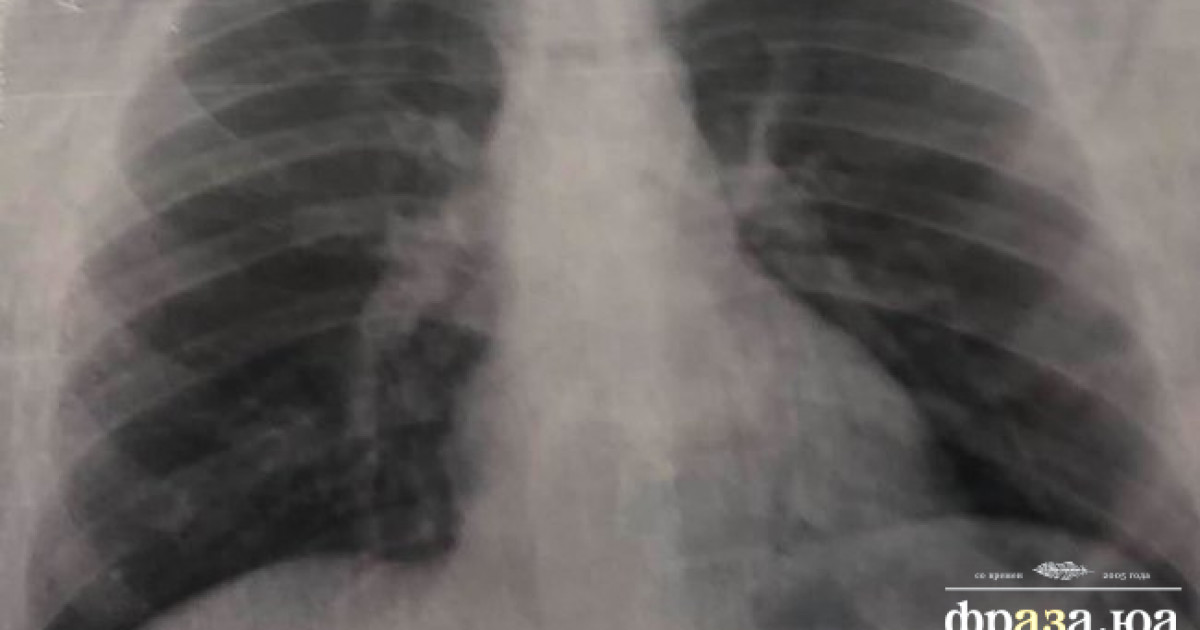

Поражение Легких При Коронавирусе Фото Рентгена

Поражение Легких При Коронавирусе Фото Рентгена 111 фото